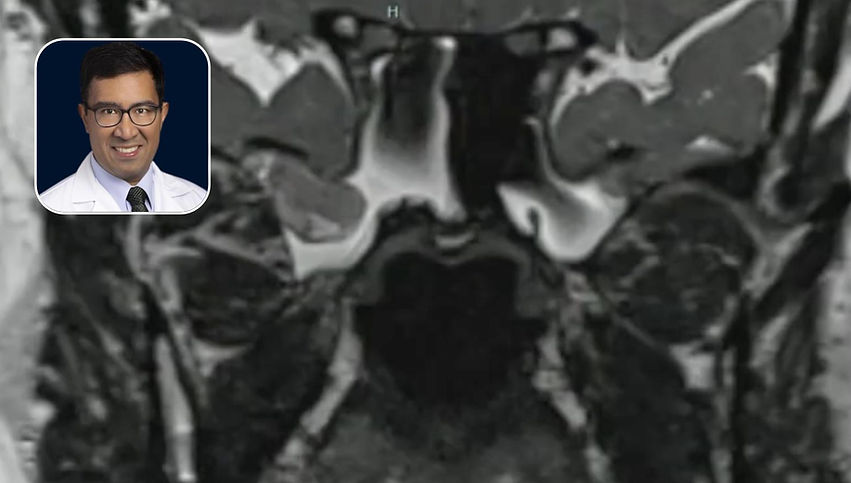

CSF Leak: Bilateral Lateral Sphenoid Recess Encephaloceles